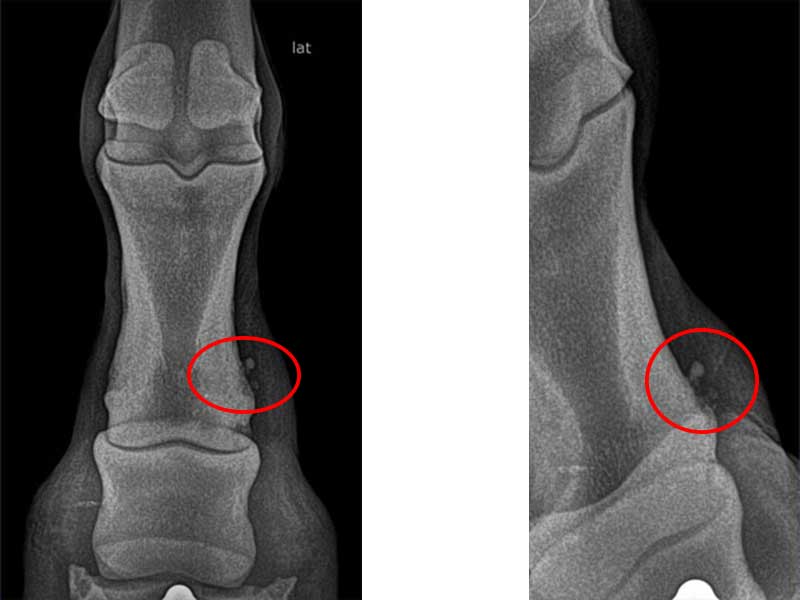

La radiología digital es una herramienta imprescindible en la valoración diagnóstica de muchos problemas equinos. En JOSE LUIS RUBIALES Veterinario trabajo con un equipo portátil de radiología digital de alta calidad, lo que permite obtener imágenes claras en muy poco tiempo y trabajar con una base mucho más precisa.

La radiología digital resulta muy útil cuando necesitamos obtener una valoración más precisa de una lesión o completar el diagnóstico de determinados problemas locomotores. Además, al tratarse de un sistema portátil, en muchos casos permite estudiar al caballo sin necesidad de desplazarlo.